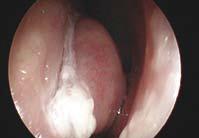

他續解釋,「鼻敏感患者長期鼻塞的其中一個原因,是由於下鼻甲骨腫脹肥大(見圖三),堵塞呼吸道所致,在這種情況下,醫生會以微創方式切除患者的部分下鼻甲骨,讓鼻腔內的通道回復正常。」

■ 圖三(圖片由香港耳鼻喉科中心提供)透過脫敏治療,可讓身體產生抗體對抗致敏源。(圖片由香港耳鼻喉科中心提供)